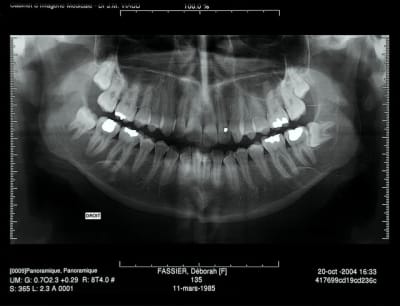

Pano demandé

> je viens de mieux regarder la pano de 2008

>

> tu connais la date précise de l'avulsion de la 38

à priori 31/03/2006 pas si vieux que ça je croyais que c'etait 2004, donc évolution rapide

ça peut être également un kyste dentigère laissé en place car il me semble que le kyste est déjà présent sur la première pano et elle est en rapport partiel avec le collet de 38 enclavée mais ça n'est pas caractéristique.

DOnc pour résumé:

1. kératokyste

2. kyste dentigère "oublié"

3. améloblastome unikystique